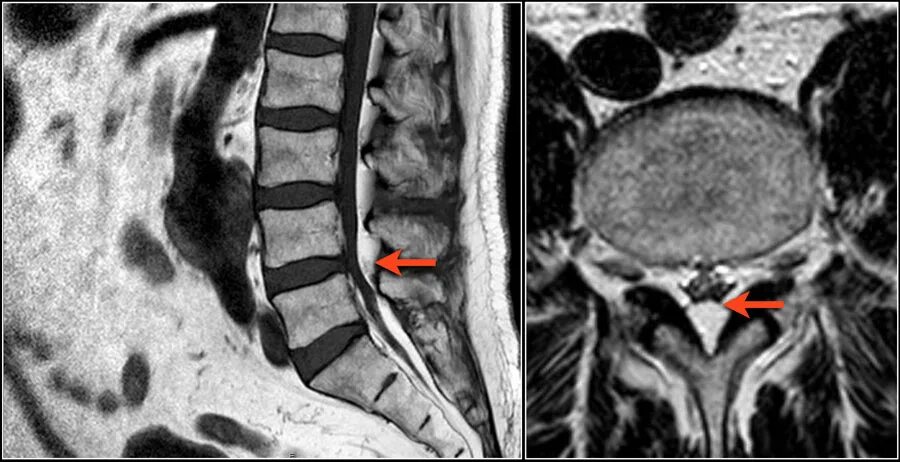

Грыжа деформирует дуральный мешок